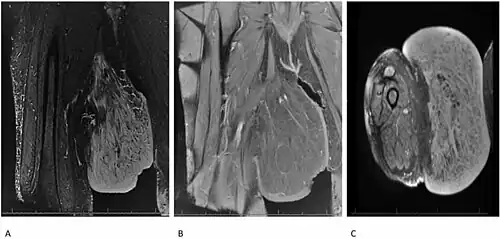

Diagnosis of Dercum's disease is done through a physical examination. In order to properly diagnose the patient, the doctor must first exclude all other possible differential diagnoses. The basic criteria for Dercum's disease are patients with chronic pain in the adipose tissue (body fat) and patients who are also obese. Although rare, the diagnosis may not include obesity.[5] Dercum's disease can also be inherited and a family medical history may aid in the diagnosis of this disease.[5] There are no specific laboratory test for this disease. Ultrasound and magnetic resonance imaging can play a role in diagnosis.[10]

- ↑ Tins, B.J.; Matthews, C.; Haddaway, M.; Cassar-Pullicino, V.N.; Lalam, R.; Singh, J.; Tyrrell, P.N.M. (27 June 2013). "Adiposis dolorosa (Dercum's disease): MRI and ultrasound appearances". Clinical Radiology. 68 (10). Elsevier: 1047–53. doi:10.1016/j.crad.2013.05.004. PMID 23809264.